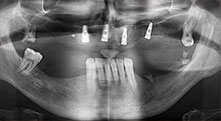

Bratu: Wir nutzen die Instrumente routinemäßig für die Entnahme von Knochenblöcken und das Spalten von Kieferkämmen. Weiterhin osteotomieren wir mit den Piezomed B6/B7 retinierte Zähne und entfernen nicht erhaltungsfähige Implantate. Alles Indikationen, bei denen es auf tiefe, saubere Schnitte ankommt.

Bratu: Wir bevorzugen Knochenentnahmen von der Linea obliqua externa des posterioren Unterkiefers, nicht aus der interforaminalen Region. Nach der Weichgewebsinzision verwenden wir die neuen Sägen, um den Umfang der Knochenentnahme zu definieren. Wir erledigen damit in fast 80 Prozent der Fälle auch die gesamte Präparation. Zusätzlich verwenden wir eventuell andere Piezo-Instrumente und zuletzt einen Meißel, um den Block zu mobilisieren. Das ist für uns eine sehr effektive Operationstechnik.